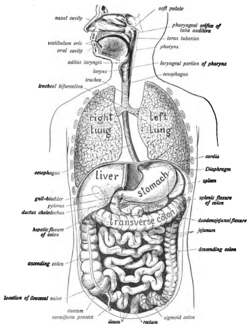

The human digestive system consists of the gastrointestinal tract plus the accessory organs of digestion (the tongue, salivary glands, pancreas, liver, and gallbladder).[1] In this system, the process of digestion has many stages, the first of which starts in the mouth. Digestion involves the breakdown of food into smaller and smaller components, until they can be absorbed and assimilated into the body.

Chewing, in which food is mixed with saliva begins the process of digestion. This produces a bolus which can be swallowed down the esophagus and into the stomach. Here it is mixed with gastric juice until it passes into the duodenum, where it is mixed with a number of enzymes produced by the pancreas. Saliva also contains a catalytic enzyme called amylase which starts to act on food in the mouth. Another digestive enzyme called lingual lipase is secreted by some of the lingual papillae on the tongue and also from serous glands in the main salivary glands. Digestion is helped by the mastication of food by the teeth and also by the muscular actions of peristalsis and segmentation contractions. Gastric juice in the stomach is essential for the continuation of digestion as is the production of mucus in the stomach.

Peristalsis is the rhythmic contraction of muscles that begins in the esophagus and continues along the wall of the stomach and the rest of the gastrointestinal tract. This initially results in the production of chyme which when fully broken down in the small intestine is absorbed as chyle into the lymphatic system. Most of the digestion of food takes place in the small intestine. Water and some minerals are reabsorbed back into the blood in the colon of the large intestine. The waste products of digestion (faeces) are defecated from the anus via the rectum.

Components

There are several organs and other components involved in the digestion of food. The organs known as the accessory digestive glands are the liver, gall bladder and pancreas. Other components include the mouth, salivary glands, tongue, teeth and epiglottis.

The largest structure of the digestive system is the gastrointestinal tract (GI tract). This starts at the mouth and ends at the anus, covering a distance of about nine (9) metres.[2]

The largest part of the GI tract is the colon or large intestine. Water is absorbed here and remaining waste matter is stored prior to defecation.[1]

Most of the digestion of food takes place in the small intestine.

A major digestive organ is the stomach. Within its mucosa are millions of embedded gastric glands. Their secretions are vital to the functioning of the organ.

There are many specialised cells of the GI tract. These include the various cells of the gastric glands, taste cells, pancreatic duct cells, enterocytes and microfold cells.